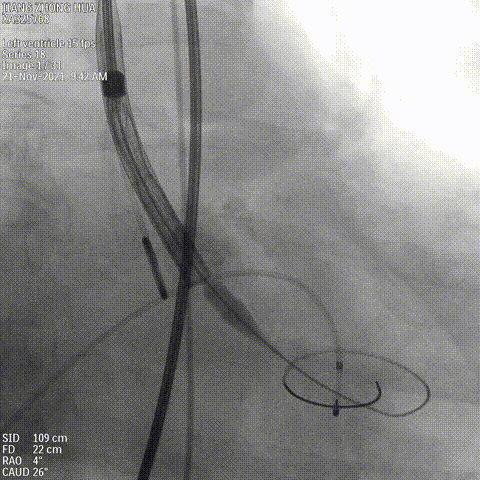

瓣膜定位